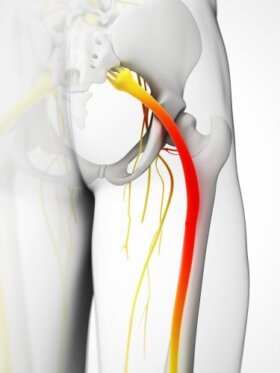

좌골신경통은 나이가 들며 누구에게나 생길 수 있는 질환이다. 매우 불편한 통증이 지속하므로, 집에서 할 수 있는 방법이 있으면 도움이 된다.…